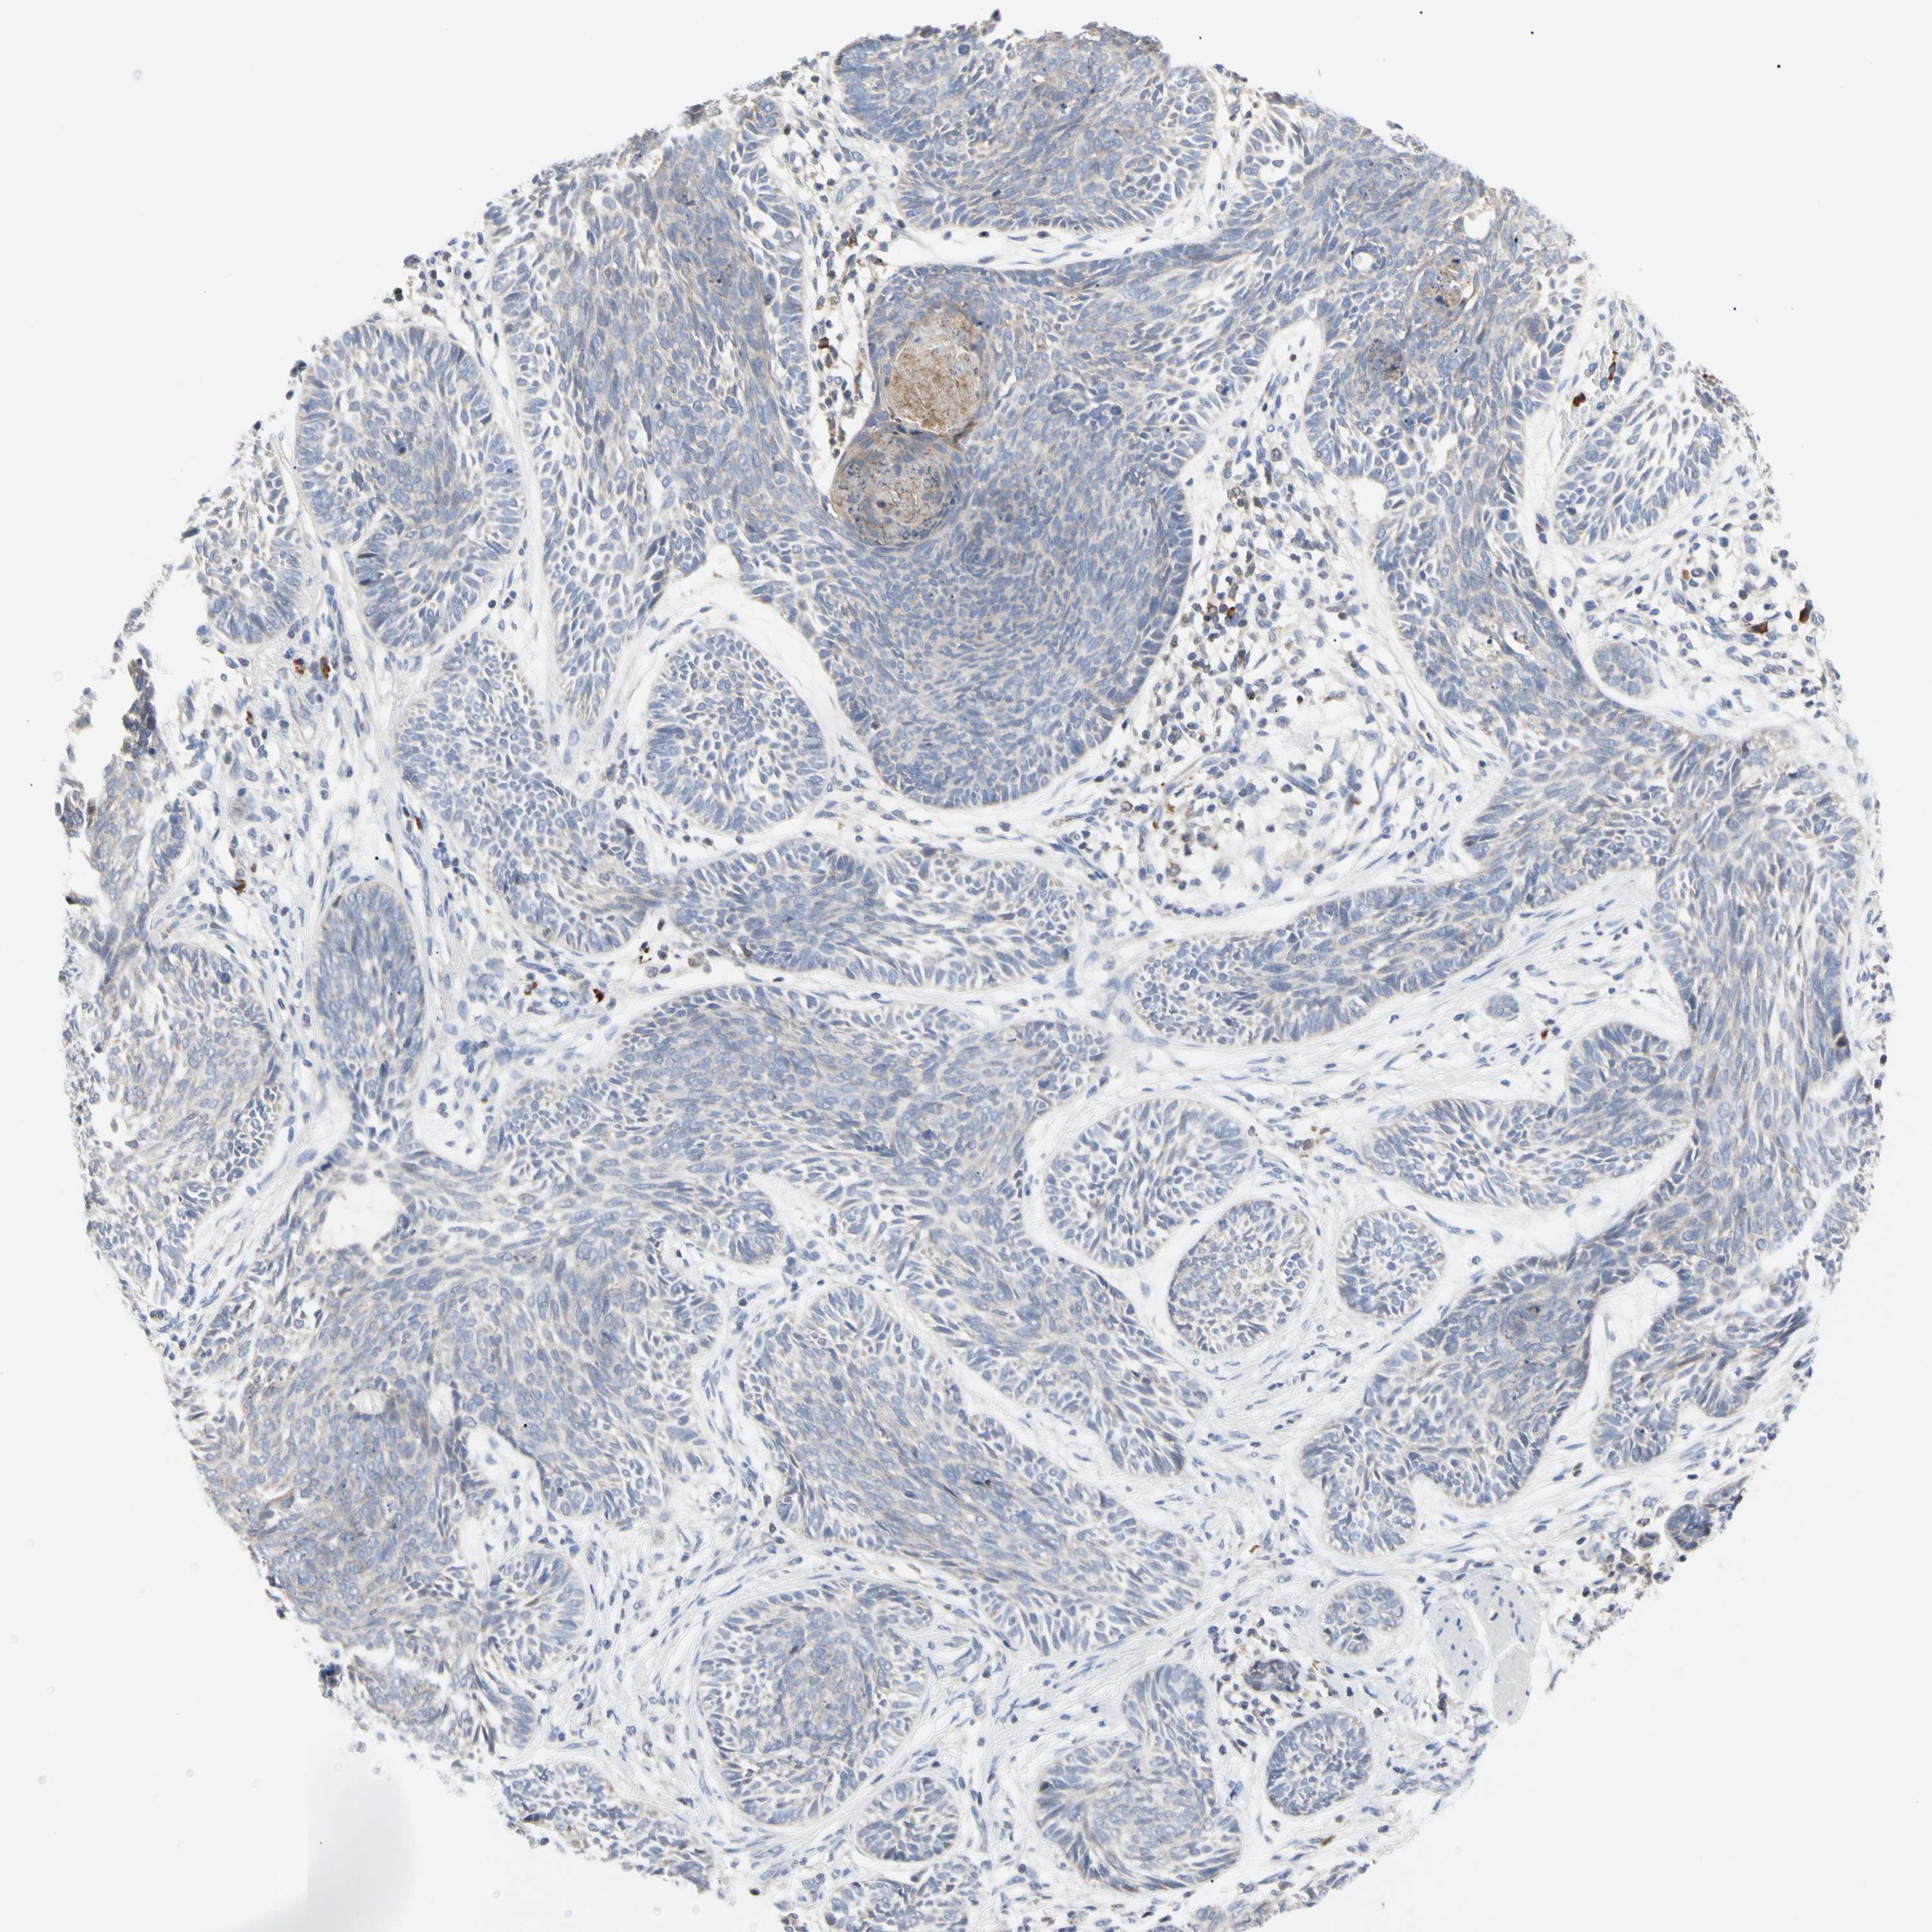

CANCER SKIN CANCER Show tissue menu

Basal cell and squamous cell cancer

SKIN CANCER - Protein expressioni

A mouse-over function shows sample information and annotation data. Click on an image to view it in a full screen mode. Samples can be filtered based on level of antibody staining by selecting one or several of the following categories: high, medium, low and not detected. The assay and annotation is described here.

Antibody stainingi

Antibody staining in the annotated cell types in the current human tissue is reported as not detected, low, medium, or high, based on conventional immunohistochemistry profiling in selected tissues. This score is based on the combination of the staining intensity and fraction of stained cells.

Each image is clickable and will lead to virtual microscopy that enables deeper exploration of all samples and also displays staining intensity scores, fraction scores and subcellular localization as well as patient and tissue information for each sample.

Antibody HPA008455

Antibody HPA031125

Antibody CAB002781

Antibody CAB068195

Squamous cell carcinoma, NOS

Squamous cell carcinoma, metastatic, NOS

Basal cell carcinoma

Papilloma, NOS